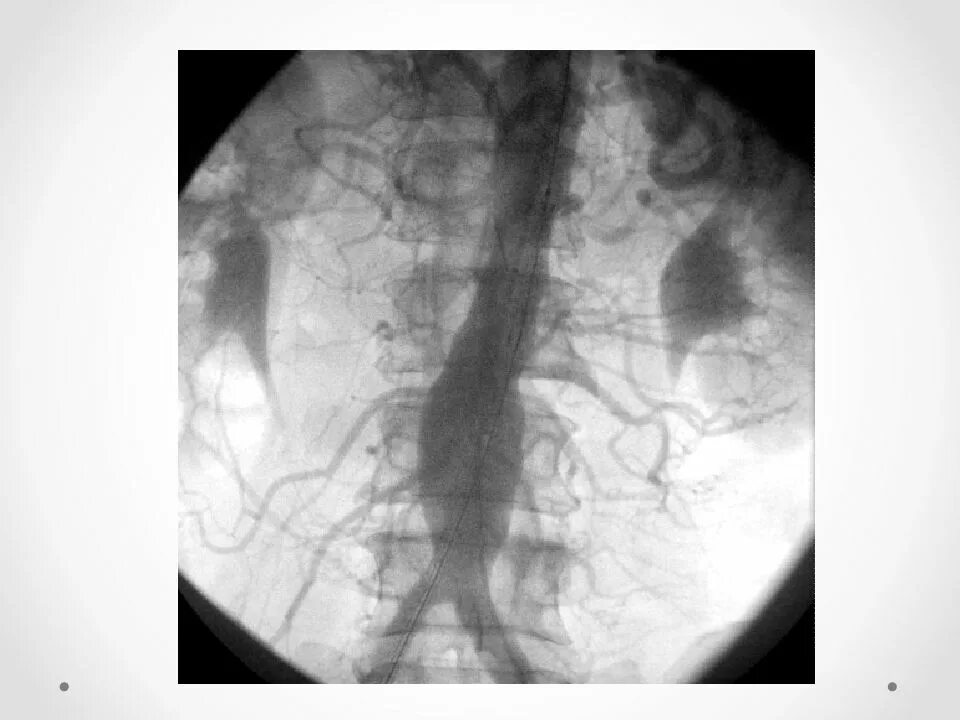

Кальциноз брюшного отдела